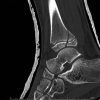

Computed tomography (CT) scan described symmetrical bony overgrowth of medial epiphysis of distal tibia with talar bony projections suggestive of DEH of distal epiphysis of tibia and talus with confirmation of secondary OA changes (Fig. 2a, 2b). Magnetic resonance imaging (MRI) scan showed the presence of bony fragments arising from the talar dome and anterior aspect of medial malleolus with no associated periosseous soft tissue and periosteal reaction suggestive of osteochondromas (Fig. 3a-3c). Surgical management was sought on as the child had difficulties in performing tasks of daily living and presented with pain and impingement after donning footwear. A medial approach to ankle was taken and malleolar osteotomy was done to have a better exposure and vision for the tumorous mass which was identified and removed from the talar dome and anterior aspect of medial malleolus. Chemical curettage with phenol was done to complete the procedure of clearance after which medial malleolus fixation with a single cancellous screw was performed (Fig. 4).